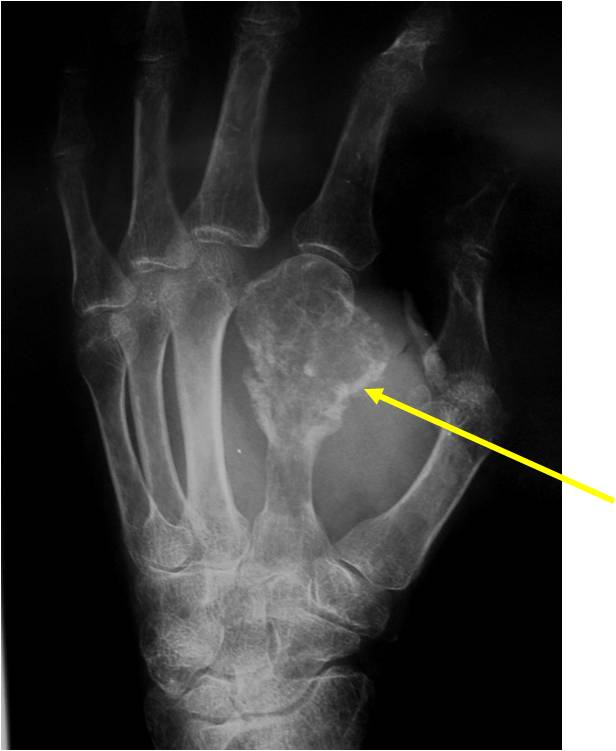

- Localized, radiolucent defect usually with punctate calcifications

- Calcifications are stippled, punctate, popcorn like calcifications and “Ring and Arc” calcifications

- Cartilage tumors grow in a lobular manner. The perimeters of the lobules undergo

- enchondral ossification that may calcify. If the entire perimeter of the lobule calcifies it appears

- radiographically as a “Ring”. If a portion of the perimeter of a lobule calcifies it forms an “Arc” on

- an X-ray.

Ring and Arc Calcifications, Minimal Endosteal Scalloping, Cortex Intact, No Soft Tissue Component, No Periosteal Reaction

Minimal Endosteal Scalloping is Acceptable

Metaphyseal Tumor, Heavy Calcifications, Ring and Arc Pattern of Calcifications, Minimal Endosteal Scalloping, No Cortical Destruction, No Periosteal Reaction, No Cortical Destruction, No Soft Tissue Component

Metaphyseal Tumor, Heavy Calcifications, Ring and Arc Pattern of Calcifications, Minimal Endosteal Scalloping, No Cortical Destruction, No Periosteal Reaction, No Soft Tissue Component